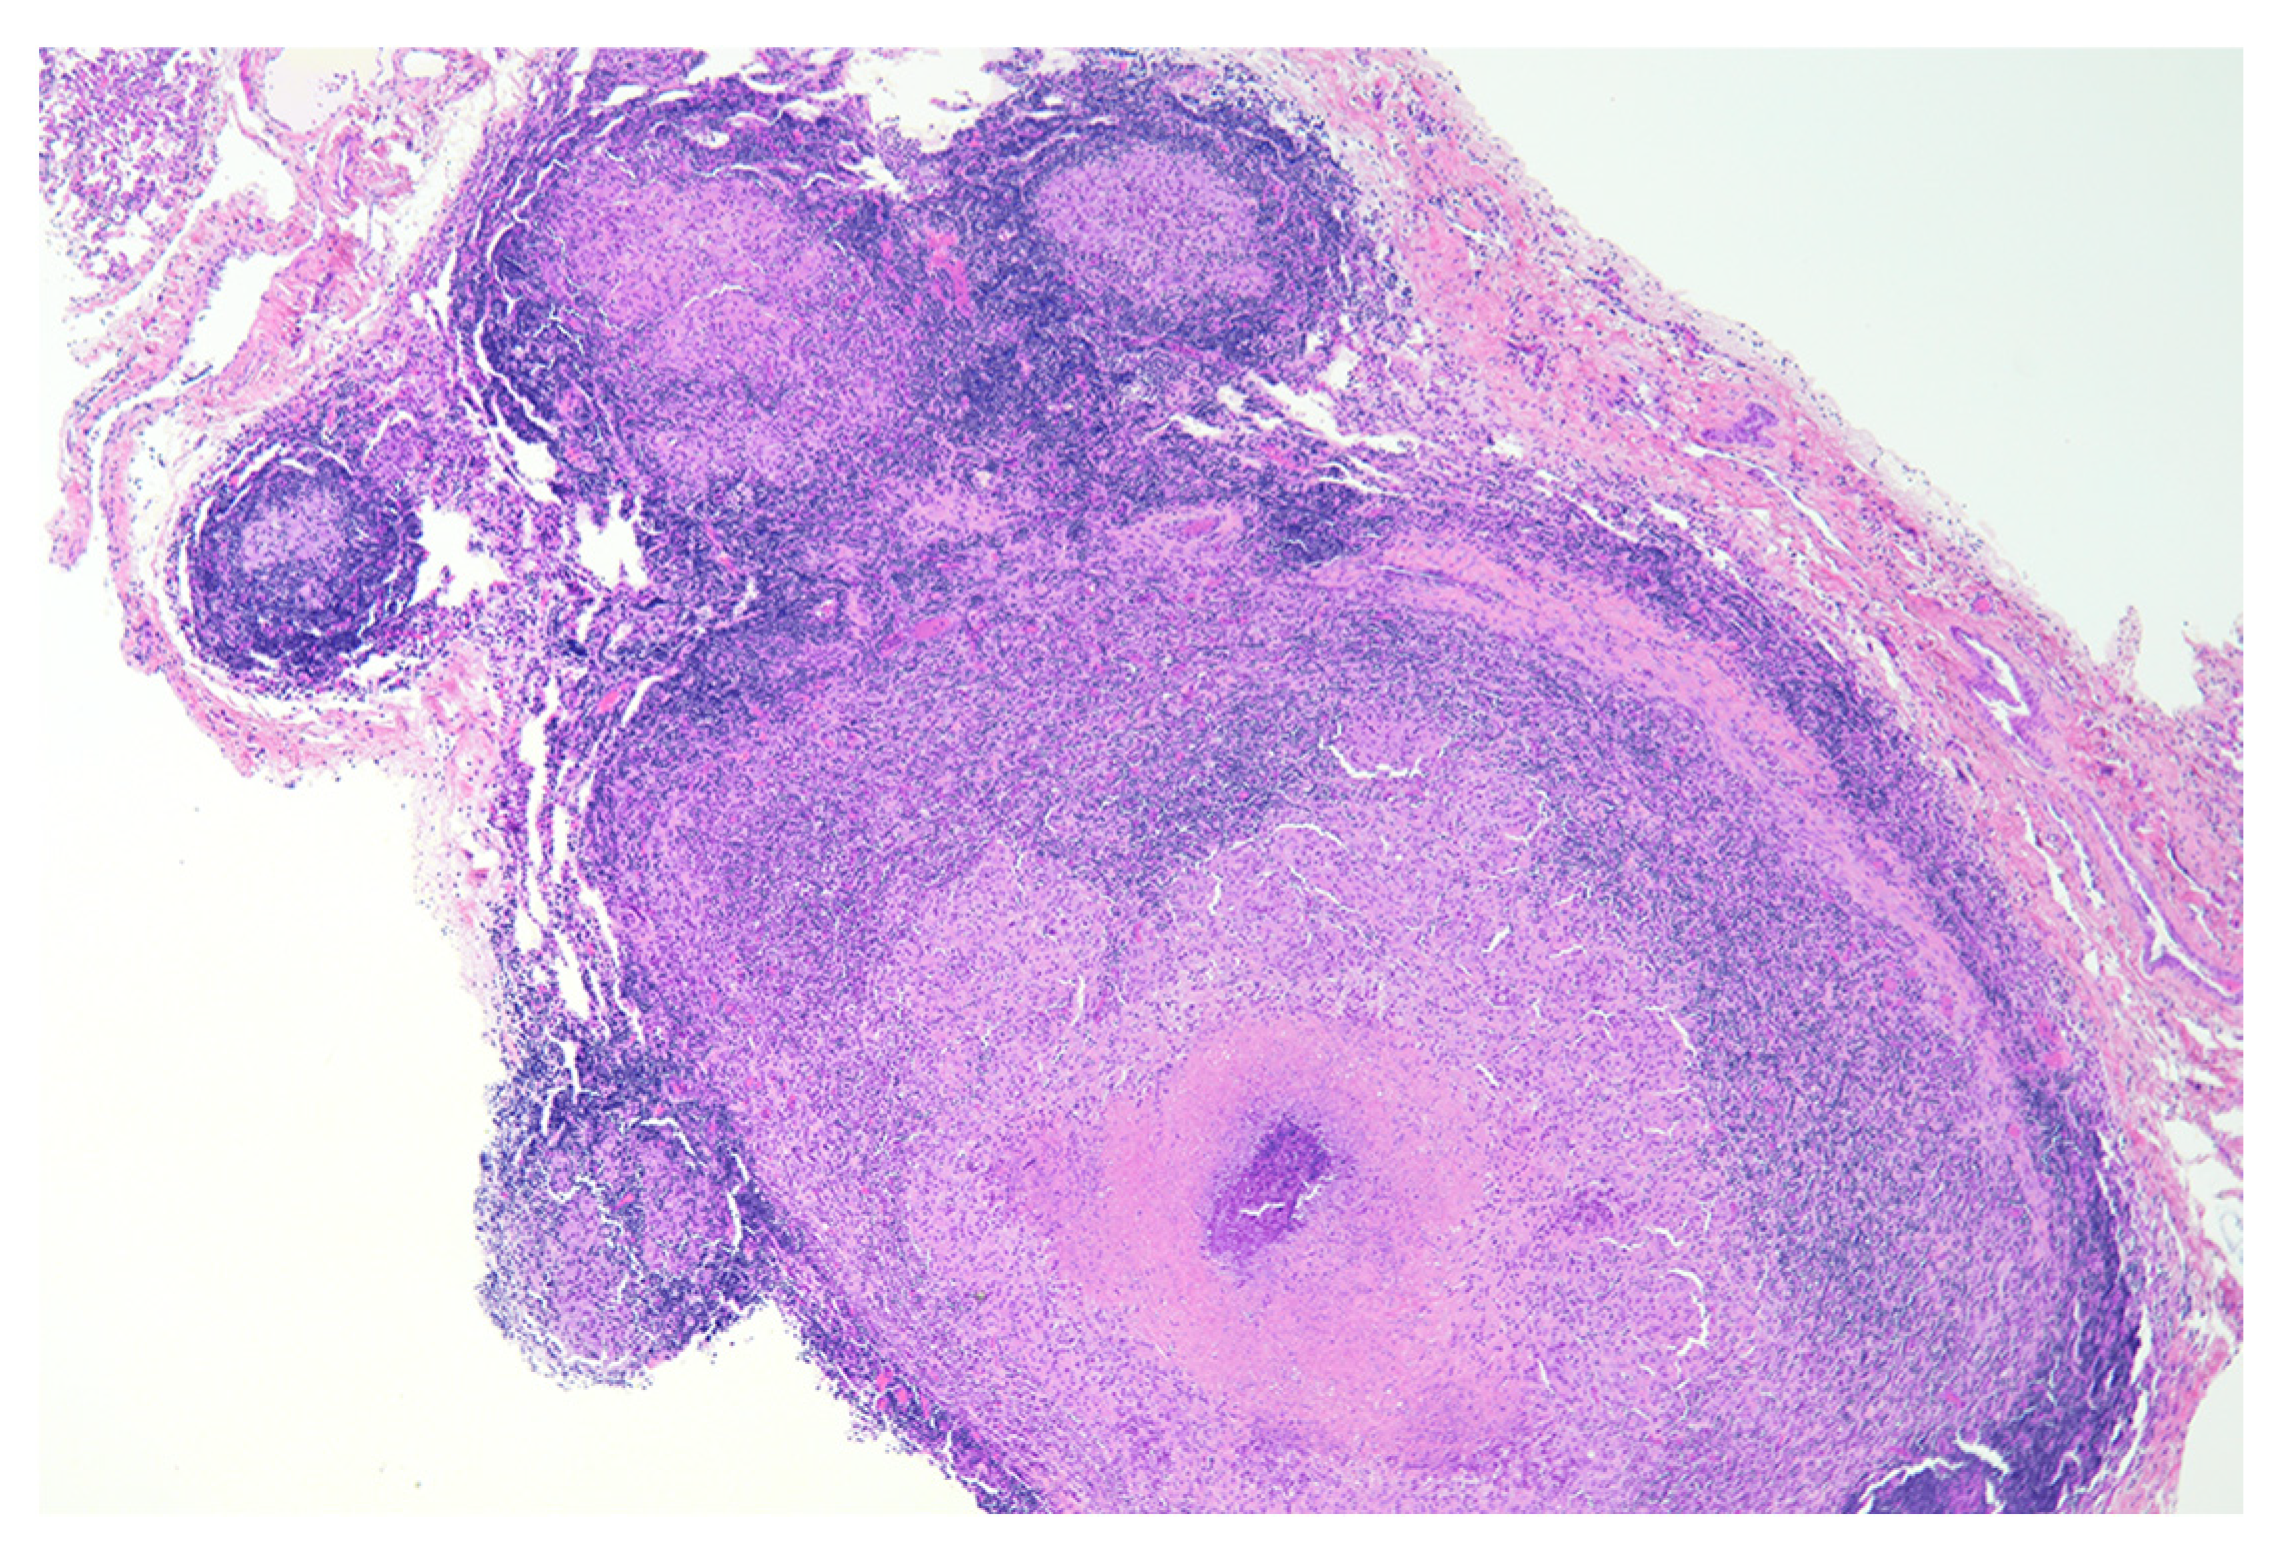

- Palmer, M.V.; Waters, W.R.; Thacker, T.C. Lesion development and immunohistochemical changes in granulomas from cattle experimentally infected with Mycobacterium bovis. Vet. Pathol. 2007, 44, 863–874. [Google Scholar] [CrossRef]

- Palmer, M.V.; Thacker, T.C.; Kanipe, C.; Boggiatto, P.M. Heterogeneity among pulmonary granulomas in cattle experimentally infected with Mycobacterium bovis. Front. Vet. Sci. 2021, 8, 671460. [Google Scholar] [CrossRef]

- Liebana, E.; Marsh, S.; Gough, J.; Nunez, A.; Vordermeier, H.M.; Whelan, A.; Spencer, Y.; Clifton-Hardley, R.; Hewinson, G.; Johnson, L. Distribution and activation of T-lymphocyte subsets in tuberculous bovine lymph-node granulomas. Vet. Pathol. 2007, 44, 366–372. [Google Scholar] [CrossRef] [PubMed]